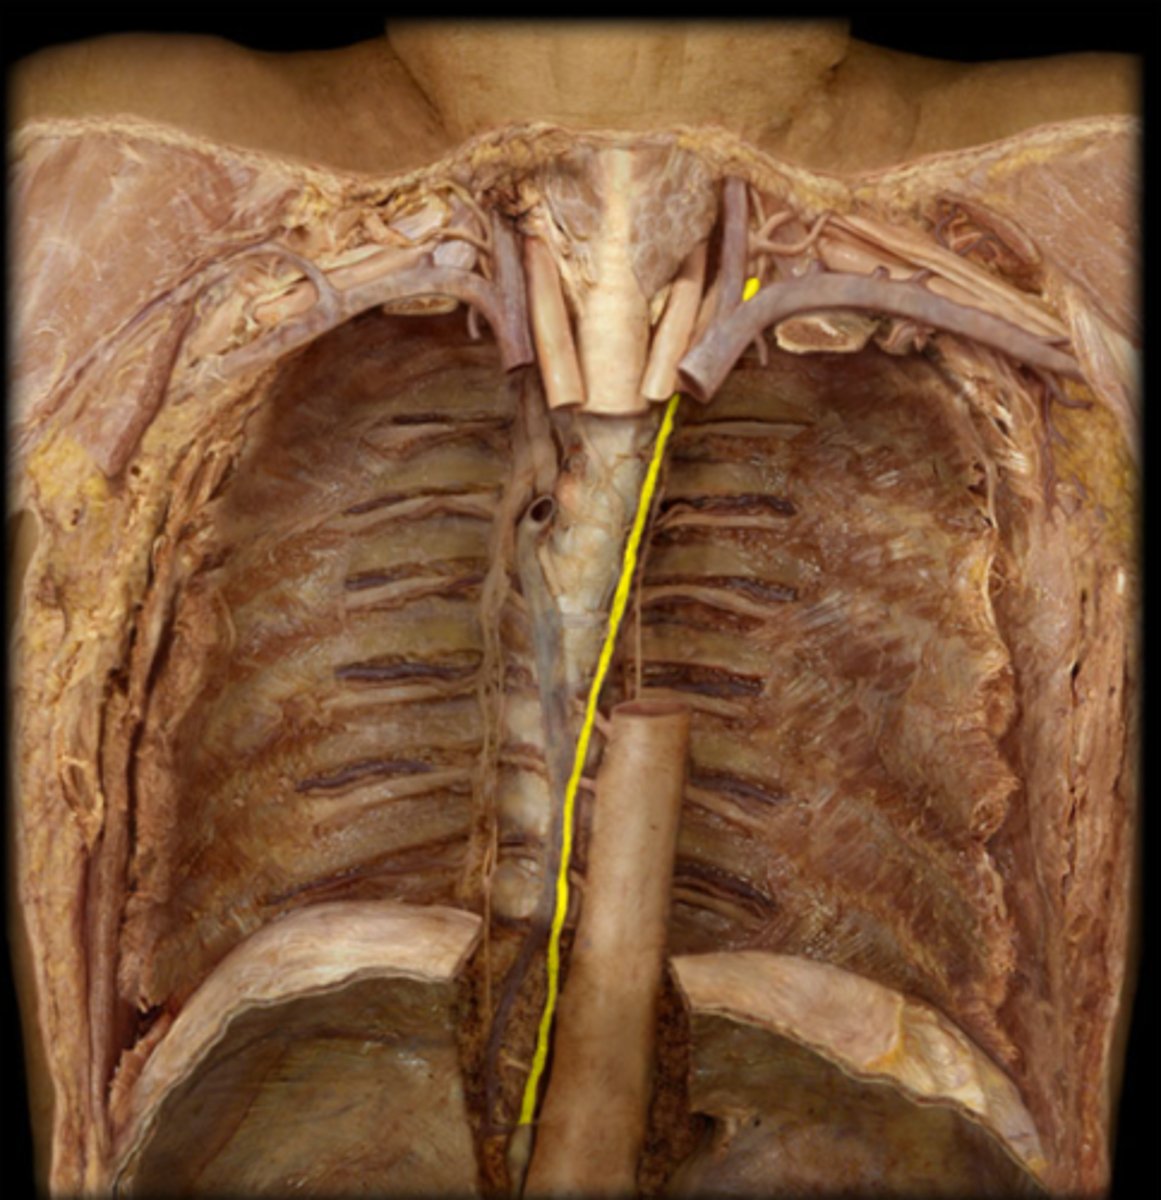

thoracic duct